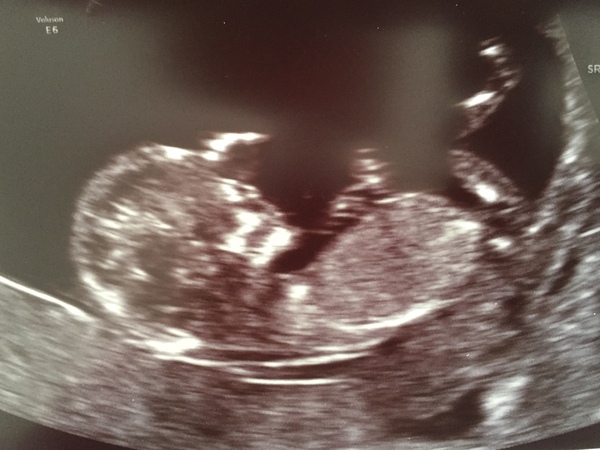

I posted on the Facebook page earlier but I had my 12 week scan today. I’m 12+2 so due on 28th Nov! Anyone left to have their 12 week scan or is that us all done now?

Hi all, here's a pic of bump at nearly 17 wks. Not feeling anything yet. Thought I felt a bit a few weeks ago but likely was just wind!

I submitted scan pics to a few nub theory pages. Mainly getting girl replies. Scan was at 12+2. Have 2 girls already and this pregnancy feels the same so not surprised at all. DH doesn't want to find out the sex this time either although ild be quite tempted! He has said he doesn't mind if I find out but not to tell him. Think ild find it way to hard knowing and him not so going to leave it.